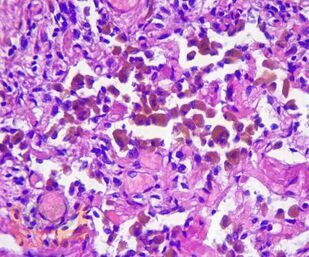

В пособии представлены цветные иллюстрации микропрепаратов и соответствующее им морфологическое описание. Детально освещены основные, наиболее важные гистологические изменения внутренних органов, позволяющие на светооптическом уровне диагностировать и дифференцировать между собой разнообразные патологические состояния. Представлены микрофотографии с гистохимическими окрасками различных тканей, использование которых помогает верифицировать специфические патологические процессы.